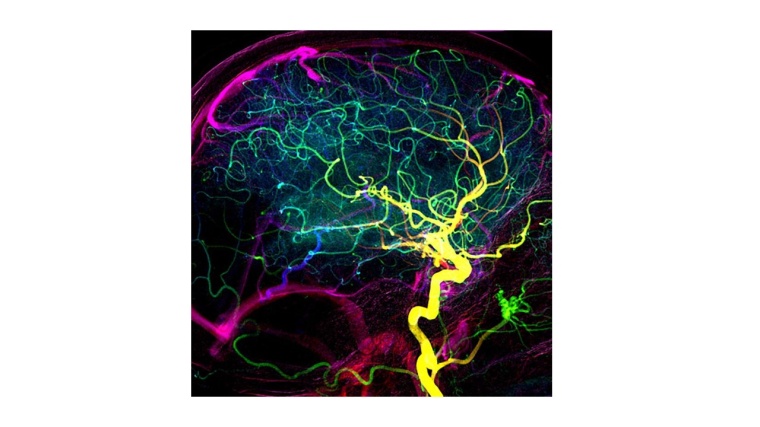

Blutgefäße, die benachbarte Arterienbäume miteinander verbinden, regulieren die Wiederdurchblutung des Gehirns nach einem Schlaganfall.

Wie Forschende der UZH zeigen, verhindern sie, dass es nach der Entfernung eines Blutgerinnsels zu Hirnblutungen kommt. Damit spielen sie eine entscheidende Rolle bei der Erholung von Patienten.

Die Forschungsgruppe von Susanne Wegener, Prof. an der Universität Zürich (UZH) und leitende Ärztin an der Klinik für Neurologie des Universitätsspitals Zürich (USZ), zeigt nun, dass der Erfolg der Schlaganfallbehandlung vom Kollateral-Netzwerk abhängt. Kollateralen sind Blutgefäße, die benachbarte Arterienbäume miteinander verbinden und als potenzielle Umleitungen im Falle einer Gefäßverstopfung fungieren. „Diese Gefäßbrücken erhalten die Selbstregulierung des Gehirns aufrecht und ermöglichen eine langsamere, allmähliche Wiederdurchblutung, was zu kleineren Infarkten führt,“ sagt Wegener.

Für ihre Arbeit verwendete das Forscherteam um die beiden Erstautoren Nadine Binder und Mohamad El Amki ein Mausmodell für Schlaganfälle sowie mehrere moderne Bildgebungsverfahren, um Veränderungen in der arteriellen Blutzufuhr am lebenden Organismus zu untersuchen. Bei Versuchstieren, die über schlechte Kollateralen verfügen, waren die Arteriensegmente nach der Gerinnselentfernung dysfunktional und starr. „Die darauffolgende übermäßige Wiederdurchblutung führte bei den Mäusen zu Blutungen und einer erhöhten Sterblichkeit“, so Wegener.

Die Ergebnisse aus dem Mausmodell konnten die Forschenden anschließend auch bei Schlaganfallbetroffenen bestätigen: Patienten mit schlechten Kollateralen zeigten nach erfolgter Öffnung des verstopften Blutgefäßes eine ähnlich schnelle und übermäßige Wiederdurchblutung des Hirnareals wie die Mäuse. Auch bei ihnen kam es zu kleinen Blutungen im Gehirn und ihre Genesung war schlechter.